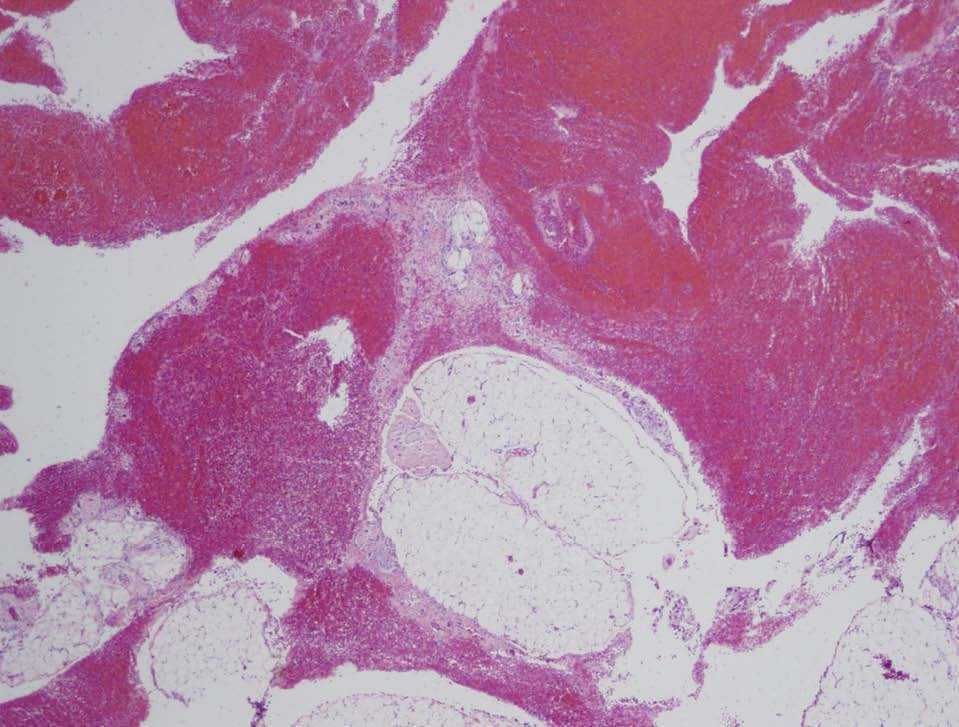

Figura 2. Tejido graso del epiplón rodeado de un gran coágulo de sangre, donde se hallaron las vellosidades coriales.

Normalmente, las gestaciones en el epiplón se dividen en 2 grupos: primarias y secundarias. En las primarias, debe encontrarse evidencia histológica de neovascularización o crecimiento del trofoblasto en el tejido de soporte. En ausencia de esta evidencia histológica, todos los casos deberían considerarse secundarios7. En nuestro caso, el examen microscópico de la pieza mostró vellosidades coriónicas dentro de un coágulo de sangre y de tejido graso del epiplón (figs. 1 y 2), aunque no se pudo objetivar ningún tipo de invasión trofoblástica del tejido del omento. Esto podría explicarse por la gran hemorragia existente en el momento de la cirugía. Aunque nuestro caso podría ser encuadrado dentro de una gestación primaria en el epiplón según los criterios clínicos de Studdiford, el examen histológico no fue decisivo a la hora de determinar si se trata de un caso de gestación primaria o secundaria en el epiplón.